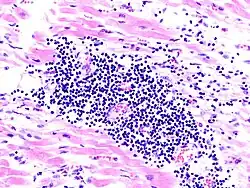

Virale Myokarditis

Mikro: Interstitielles lymphozytäres Infiltrat (kleine blaue Zellen), kaum Nekrosen.

Virale Myokarditis bei Patient mit plötzlichem kongestiven Herzversagen, Autopsiepräparat, H&E.

idem.